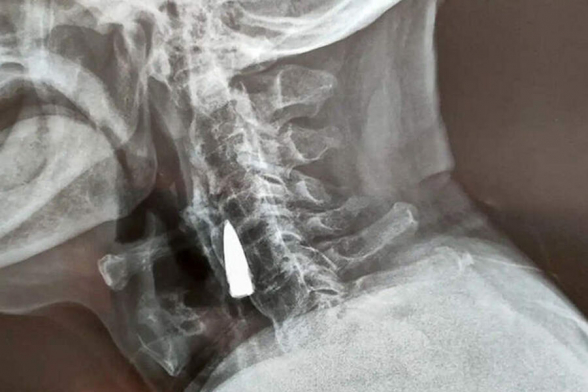

Чжао Хэ пожаловался семье на дискомфорт в шее. Родственники отвезли мужчину в больницу, где ему сделали рентген, чтобы узнать, что могло быть источником боли. Только вместо этого врачи с удивлением обнаружили там пулю, посмотрев снимок пациента.

Сам Чжао считает, что пуля находится в его шее с 1944 года. Снаряд пробил ему верхнюю челюсть и выбил несколько зубов, после чего застрял рядом с горлом. Проведя совещание, медики решили, что патрон лучше не доставать – рядом находится много кровеносных сосудов. Ветеран согласился с этим решением.